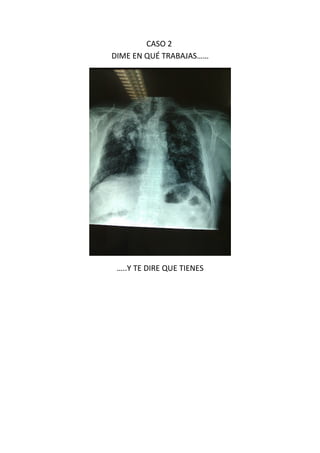

Este documento presenta 7 casos de patología torácica que serán discutidos en una sesión de interpretación radiológica. El objetivo es que los asistentes tomen notas aclaratorias durante la discusión interactiva de cada caso, en lugar de una mera explicación teórica. Los casos incluyen agenesia pulmonar derecha, situs inversus, estridor, neumonía con hemoptisis y enfermedad intersticial. El último caso involucra a un paciente de 86 años con tos y disnea que podría tener una consolidación en la base